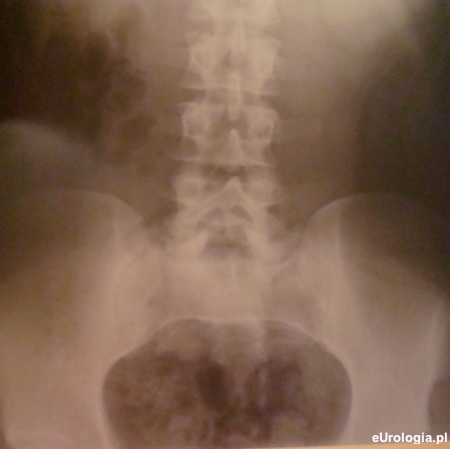

Fot. Zdjęcie przeglądowe jamy brzusznej.

Złogi 3 mm w dolnym kielichu nerki nie są przyczyną dolegliwości. Przesłane zdjęcie jest bardzo niskiej jakości i jest technicznie nieudane - nieuwidoczniono L1/L2 + obciete spojenia łonowego. Decyzję o ewentualnym przyspieszeniu wizyty u urologa proszę pozostawić lekarzowi rodzinnemu, który zbada pacjenta i będzie miał możliwość wglądu do wykonanych badań.